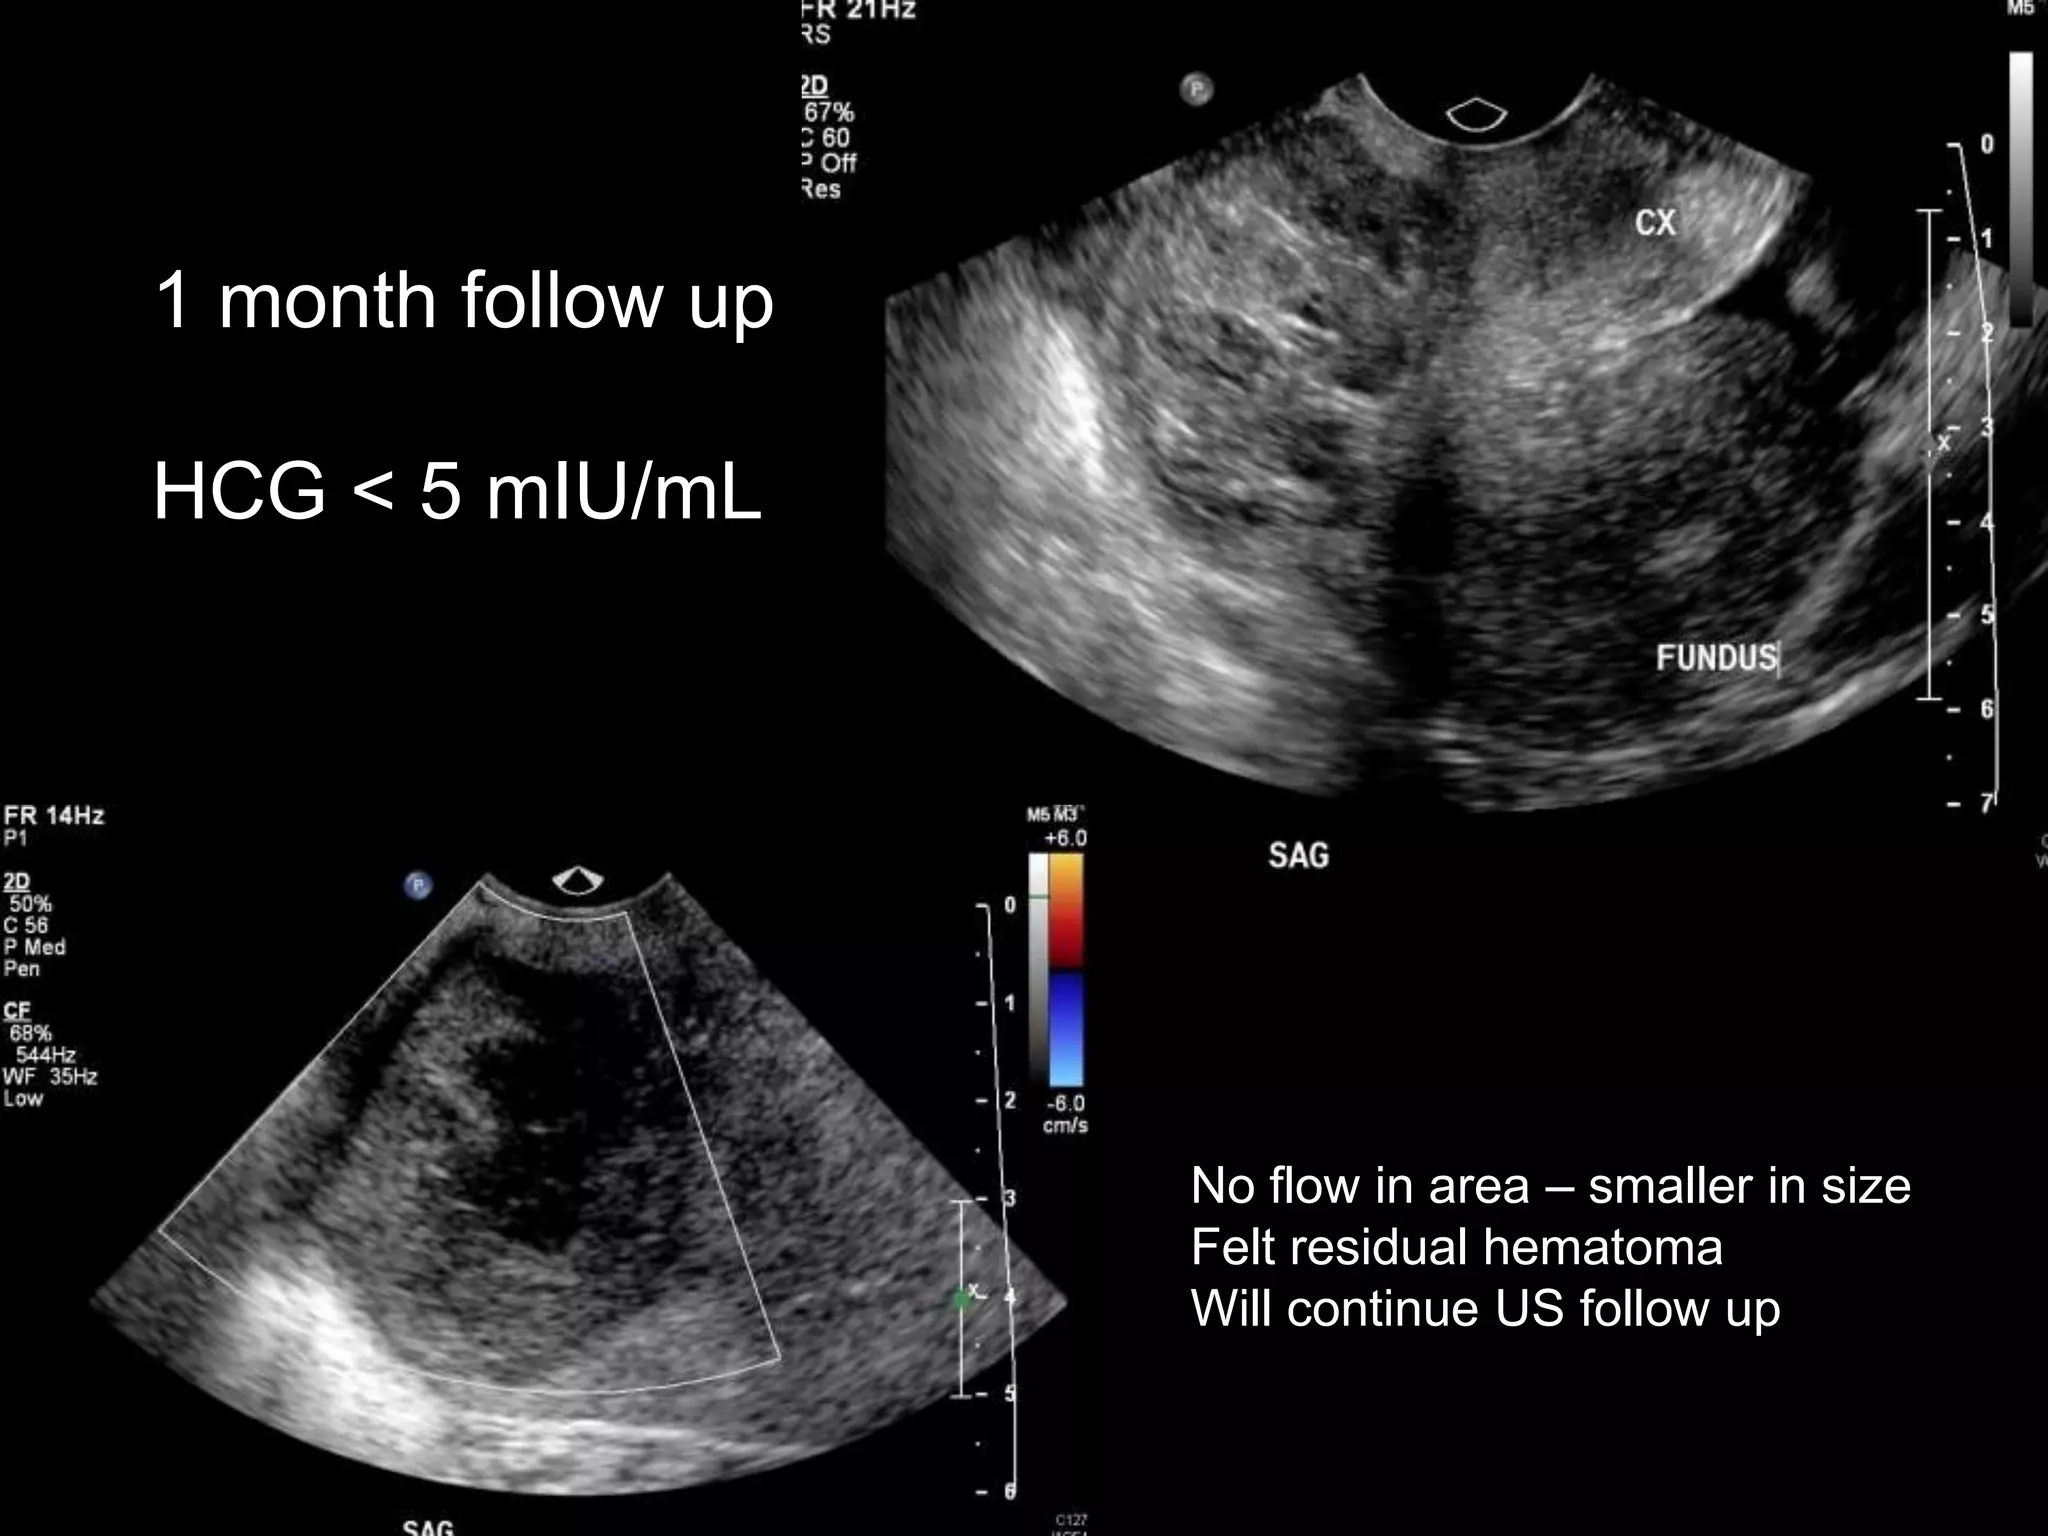

1 month follow up

HCG < 5 mIU/mL

No flow in area โ€“ smaller in size

Felt residual hematoma

Will continue US follow up